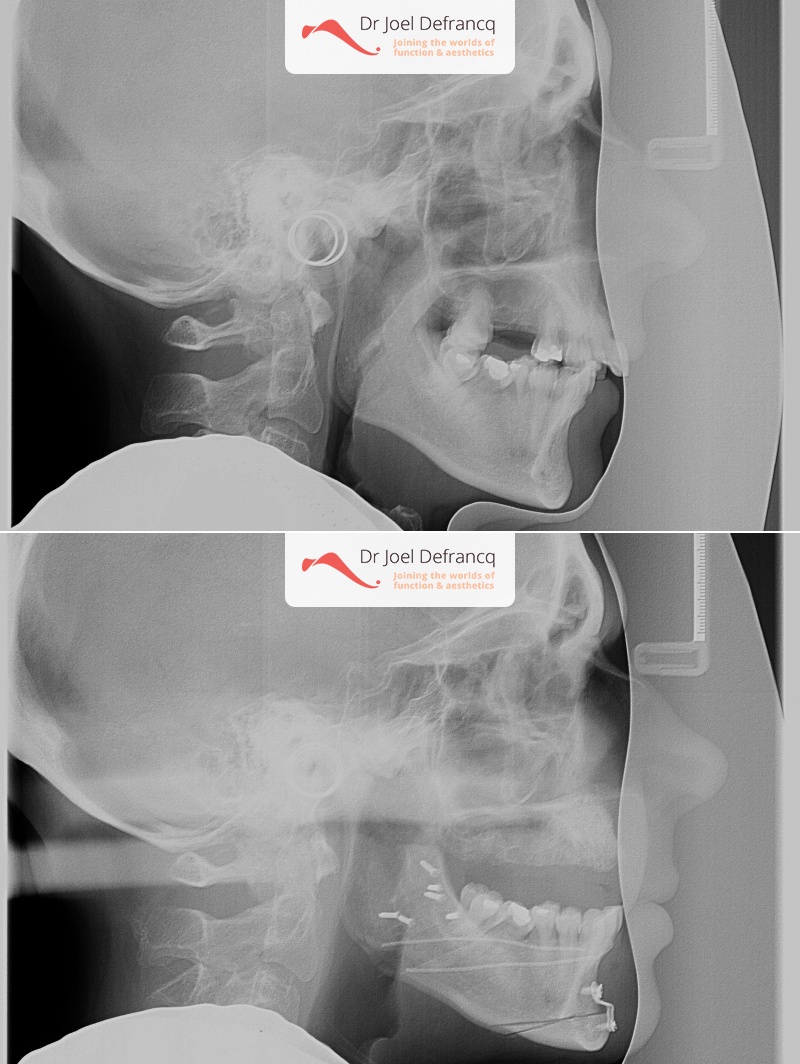

Diana: : Overbeet - diepe beet, smalle bovenkaak - lipofilling

- Te kleine onderkaak (Overbeet)

- Te lange bovenkaak

- Verlenging onderkaak (BSSO)

- Vertikale verkorting bovenkaak (Le Fort I)

- Kinchirurgie